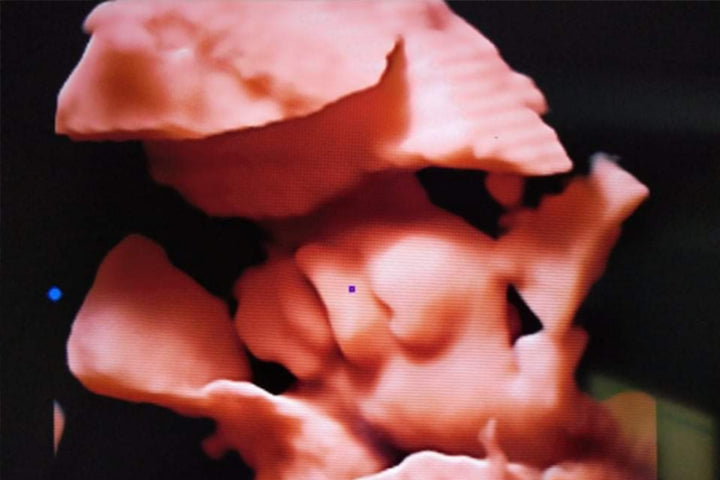

La imagen muestra los comentarios enviados por la Clínica SAMBO AMATA, un hospital privado de Camboya, después de utilizar un nuevo instrumento de ultrasonido portátil 5D especialmente diseñado para mujeres embarazadas: el DW-P5pro. El sueño de Dawei desde hace mucho tiempo es poder enviar un "equipo de asistencia médica que nunca se vaya" a Camboya, y esta retroalimentación es un gran paso en el camino hacia la realización de Dawei.